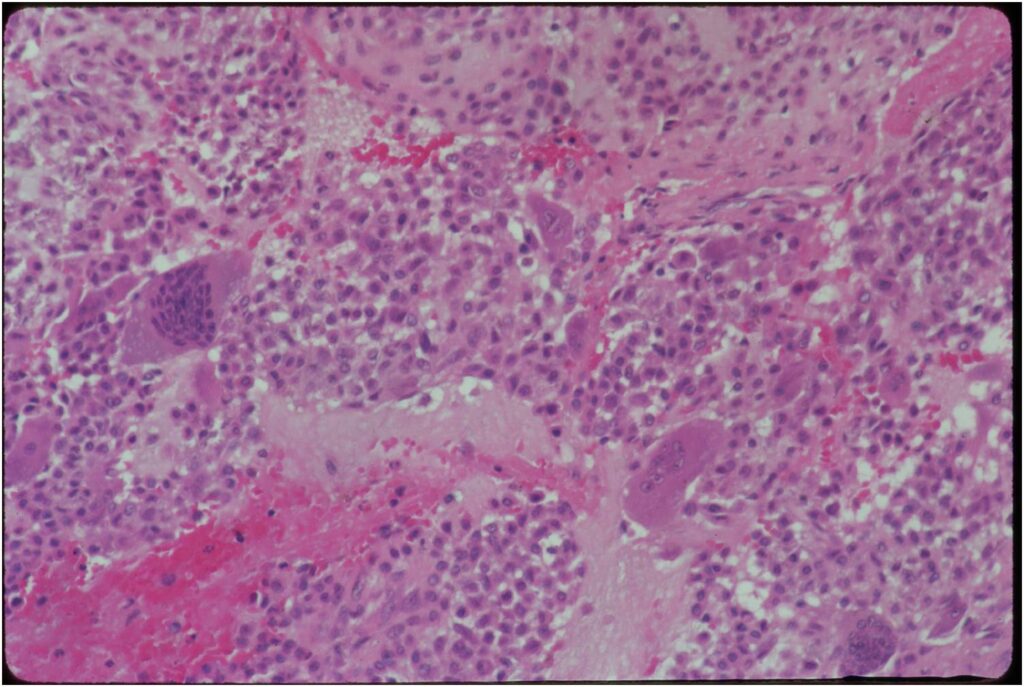

Microscopic Pathology

- Variable appearance depending on percentage of cells, necrosis, cartilage matrix formation and ABC change

- Chondroid matrix in up to 15% of tumor

- ABC component 5-15% of tumors

- The tumor is composed of chondroblasts that have a distinct, thick cell membrane. The thick cell membrane gives it a “Chicken Wire Fence Appearance,” especially when the cell membranes are calcified